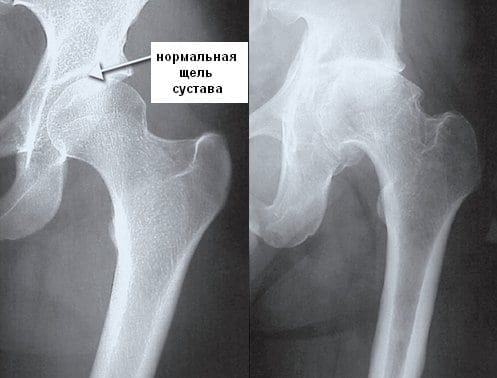

В диагностике ревматизма наиболее информативны серологические и бактериологические исследования: определение уровня С-реактивного белка, обнаружение повышенного титра антител. Для выявления степени повреждения суставов проводятся рентгенография, МРТ, КТ. Лечение консервативное с использованием иммунодепрессантов, глюкокортикостероидов, нестероидных противовоспалительных препаратов.

Рентгенография, КТ, МРТ проводятся для оценки состояния суставных структур, исключения других воспалительных и дегенеративно-дистрофических патологий. Также необходима дифференциальная диагностика с туберкулезом, неврозами, неспецифическим эндокардитом.